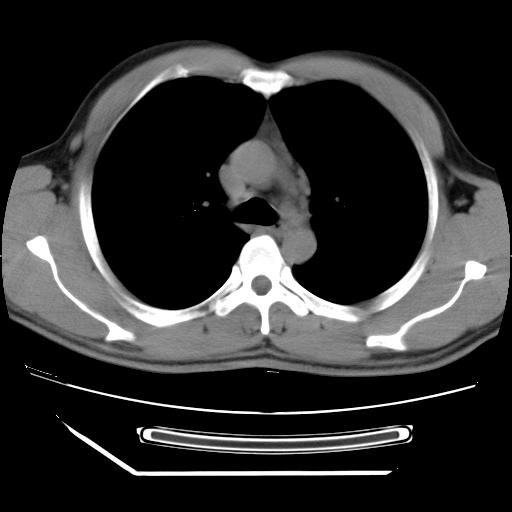

病灶发生在下叶,密度均匀,边缘模糊、毛糙,周围血管纹理增强扭曲改变,靠近胸膜处病灶胸膜反应明显。

支持考虑---球形肺炎。

虽然实验室检查支持炎性病变,且病变内有坏死改变(中央呈大片状低密度影),但仍不能掉以轻心,鳞癌也可以有这种影像改变。